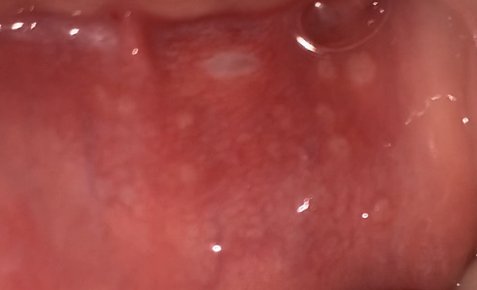

[혐주의]

입안에 이싱한거 생겼는데 혹시 먼지 아는사람

뭔 오돌토돌 동그랗게 하얀것들이 막 생겻듬ㅠ